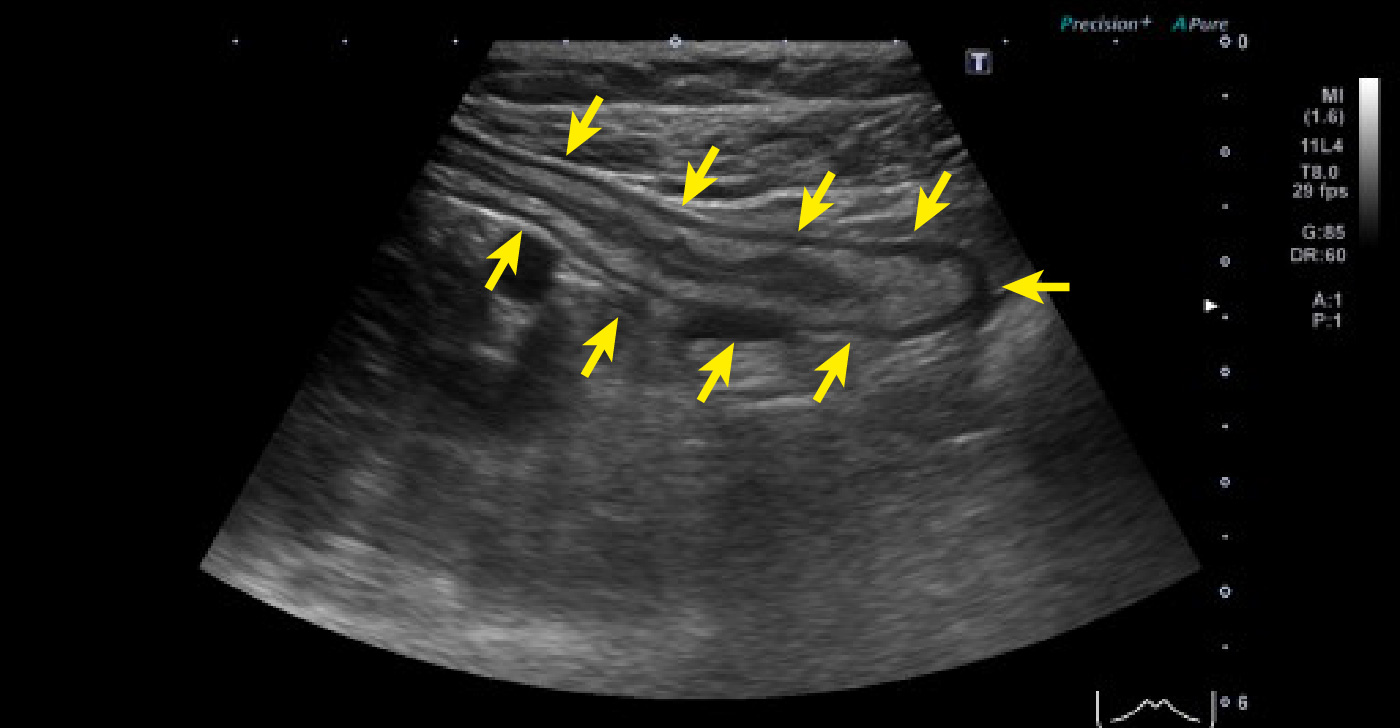

上行結腸から背側へ突出した憩室と憩室内結石~腹部エコー